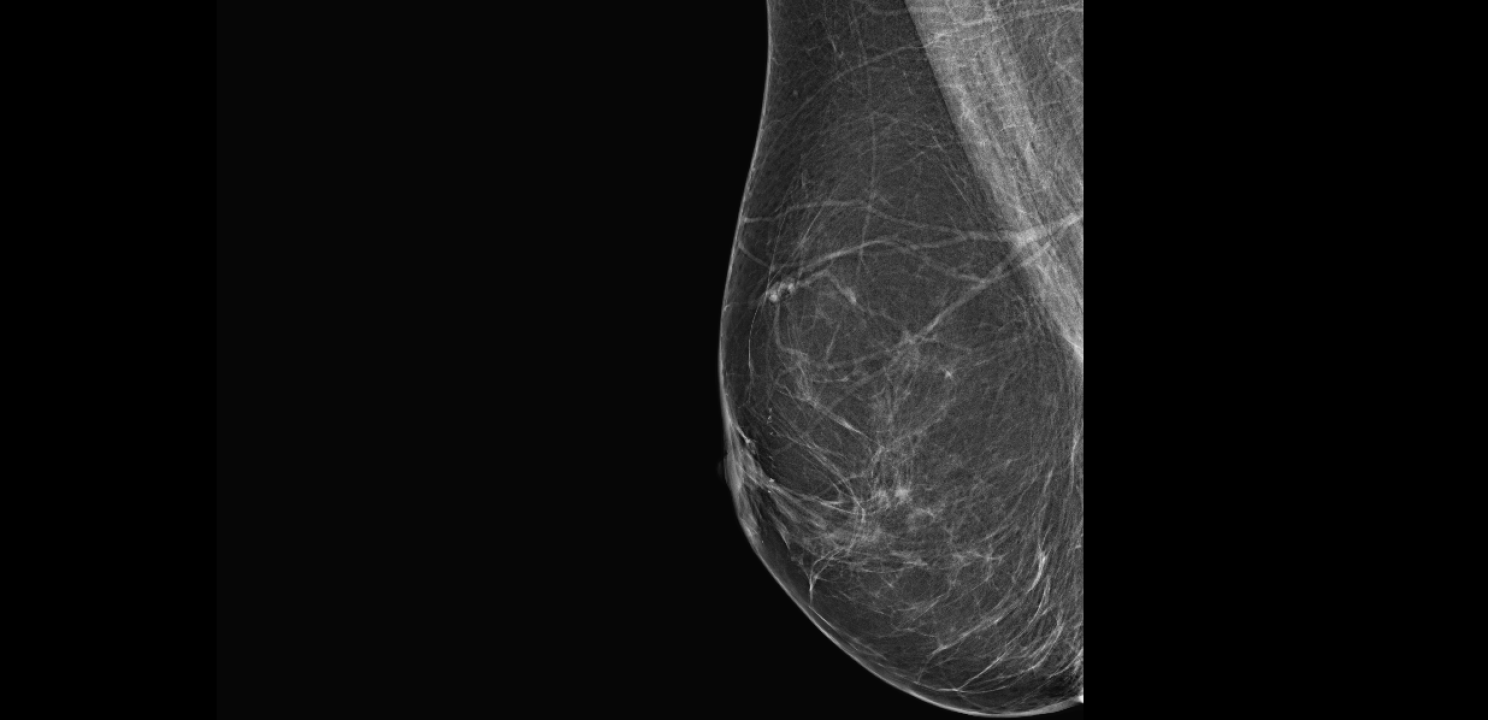

Povodom mjeseca borbe protiv raka dojke

Poliklinika Affidea Vita svojim pacijenticama nudi besplatne preglede dojki!

Listopad je mjesec borbe protiv raka dojke, jedne od najčešće dijagnosticiranih zloćudnih bolesti kod žena.